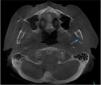

Regarding the imaging aspects of the jawbones in the MM group, solitary or multiple hypodense lesions suggestive of bone involvement were observed in 31 (73.8%) patients. In 28 (83.1%) patients, there were large lesions, with poorly defined margins, with a typical pattern of plasmacytoma. Minor multiple hypodense lesions, exhibiting sclerotic margins, named “punched out” lesions, were observed in the images of 5 (16.1%) patients (Figure 2). Cortical disruption was observed in 7 (22.5%) patients (4 in the upper jaw and 3 in the lower jaw) (Figure 3). The lower jaw was affected in 16 (51.6%) patients and both upper and lower jaws were affected in 15 (48.3%) cases.

Jawbone lesions in MM are commonly mentioned and have been reported as one of the first detected signs of the disease.5,6,8,13–16 Similarly to the results of this study, plasmacytoma lesions6,8 have been described more often than the typical pattern of “punched out” lesions.3,17 Plasmacytoma lesions have been characterized as large and irregular radiolucent lesions, with poorly defined margins.6,8 “Punched out” lesions are commonly visualized as multiple and rounded radiolucencies with no corticalized well-defined margins.3,17 The jawbone lesions are not pathognomonic of MM. Differential diagnosis with other maxillary pathological conditions, such as chronic osteomyelitis, osteonecrosis, osteoradionecrosis, ameloblastoma, osteosarcoma, Paget's disease and other conditions, should be considered in the evaluation of the jaw images.

The majority of MM patients (73.8%) presented jawbone lesions suggestive of MM, as observed in the CBCT images. Other studies have reported smaller frequencies of jawbone lesions, varying from 5.18% to 15.60%.3,8,17 Most of the studies described the imaging aspects of MM mainly in panoramic radiographies,2,6,8,18 while others used intraoral radiographies,2,4,8 computed tomography5 and magnetic resonance imaging.2,5 The high number of jaw bone lesions identified in this study suggests that CBCT is more sensitive than other imaging methods in the detection of myelomatous lesions in the jawbones. The significant correlation between the presence of the bone lesions suggestive of MM in the jaws and other bones suggests that CBCT imaging is a powerful tool in the jaw evaluation of patients with MM. Because of a three-dimensional view of the jawbone, CBCT imaging may show more details, presenting good accuracy, without overlays, and deliver smaller radiation doses than conventional computed tomography. To our knowledge, only one study evaluated the maxillofacial complex of patients with MM using the CBCT as a tool to analyze possible lesions due to multiple myeloma, and found similar results.2

The mandible was affected in nearly half of the patients with MM presenting jaw lesions, and the other half presented simultaneously affected lower and upper jaws. No other study reported lesions in both upper and lower jaws at the same time. Some case reports report the mandible,6,17,18 while others report the maxilla,2,4,5,19 as the most affected gnathic bone in patients with MM.